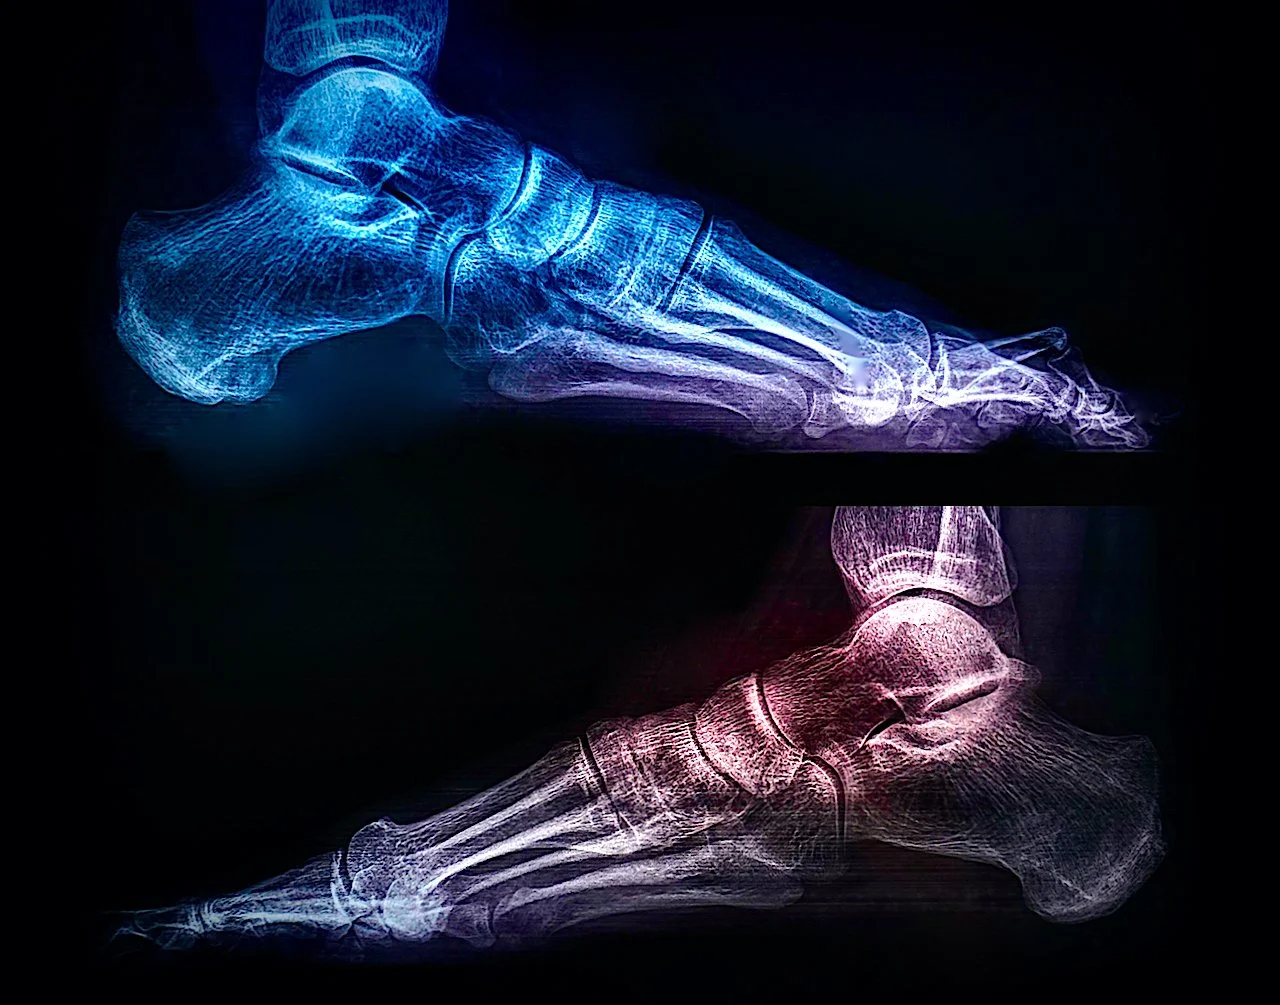

saturday night fever (girl meets boy diptych)

Selected for July/Aug 2022 exhibition in Art No.23’s Barcelona gallery.